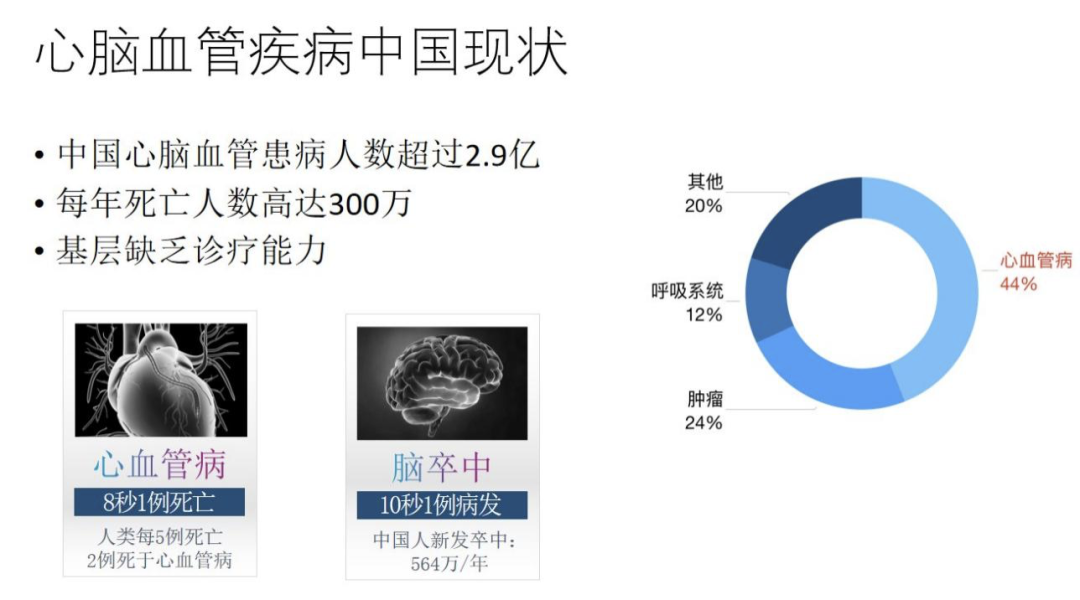

下面我以一个比较有代表性的 2.0 产品为例作详细的介绍,希望能让大家理解如何做出一个有价值的 AI 影像产品。这个产品聚焦于心血管或脑血管疾病的诊断。选择这两种疾病的原因是心脑血管疾病是非常高发,并且后果严重的重要疾病。在中国这两种病的死亡率也很高,基层医院普遍缺乏诊疗能力,对设备和医生的能力要求都很高,只有少数大医院才能对血管做很好的疾病处理。提升大医院、小医院对心脑血管疾病的处理能力,对整个医疗现状很重要。